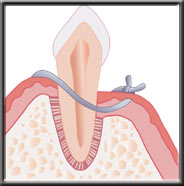

In more moderate cases, there is actual bone loss, and deeper pockets. Non-surgical scaling and root planing may remove the calculus from these deeper pockets but because of limited and difficult access in reaching the bottom of the pocket some of these cases may need flap surgery.This allows us to gain access to clean the root. With this procedure, an incision is made between the gum and tooth, and the gum moved back away from the neck of the tooth and the edge of the bone. We can then easily see the deep calculus, and adequately clean the tooth.

Flap reflected to access deep plaque and calculus |

After flap surgery the tissue may be returned to its former position, which minimizes cosmetic changes. However, because the gum can not connect back to the tooth, this does not eliminate the pocket. With the pocket remaining, the patient cannot remove all the bacteria, and must rely on frequent hygienist cleanings to help control reoccurrence of the infection.

Flap returned to normal |